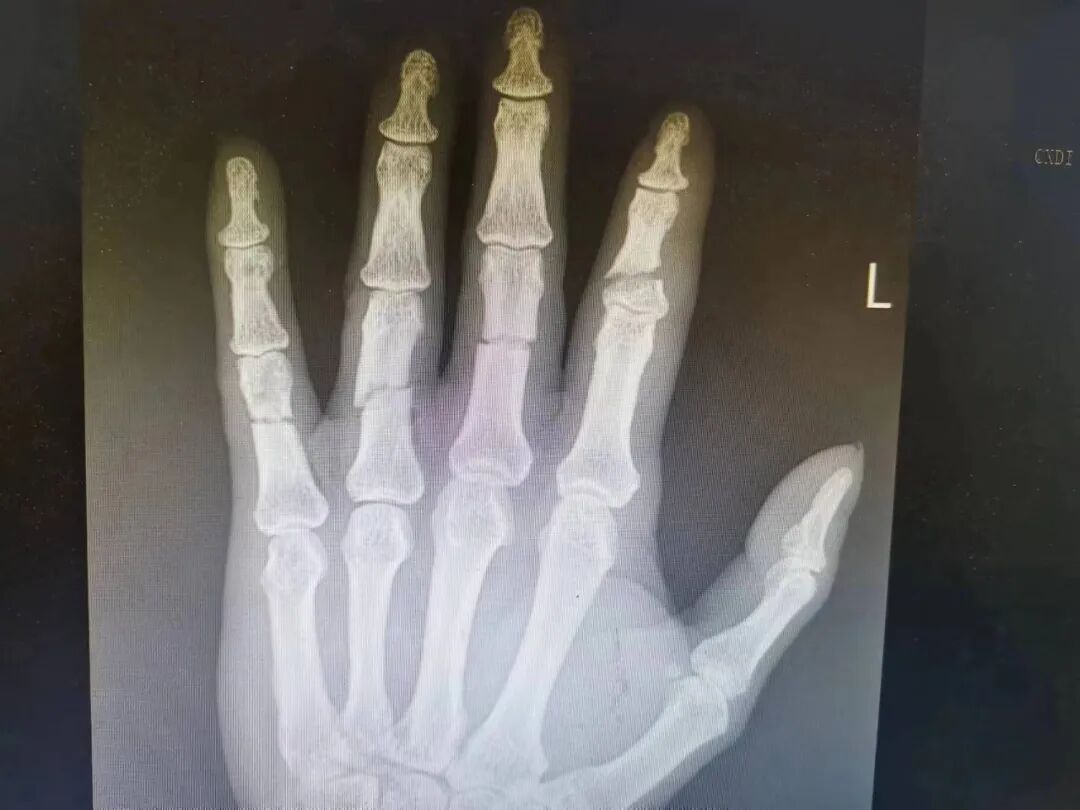

/// 那么当我们受伤时,如何去判定是否需要上医院呢? 首先你得观察你伤口的面积与深度,然后检查让你受伤的元凶。如果只是小范围表浅的伤口且造成你受伤的物品是清洁的,你可以自已消毒后贴个创口贴。但是由于手部的结构非常精巧而复杂,除了上述情况外,我们都需要求助医生的判断。 “ 小范围浅表伤口 到了医院后,你会接受到医生专业的检查。 首先是皮肤损伤的检查,包括:创口的部位和性质、皮肤缺损的估计、皮肤活力的判断。其中皮肤活力的判断又包括:观察皮肤的颜色和温度、毛细血管回流试验、观察皮瓣的形状和大小、观察皮瓣的长宽比例、观察皮瓣的方向、观察皮肤边缘出血的状况等;其次还有肌腱损伤的检查、神经损伤的检查、血管损伤的检查和骨关节损伤的检查。 这些检查多数是需要清创后才能判定的,清创的目的就是清除伤口内的污染物和异物,去除失活的组织使污染的伤口变成清洁的伤口以预防感染,更有助于对伤口各种损伤的判定,以便接下去制定手术方案。 骨干及关节损伤判定除了借助仪器外还有以下方法: 1.畸形:骨折端移位可以使患者外形发生改变,主要表现为缩短、成角或旋转。 2.异常活动:正常情况下肢体不能活动的部位,骨折后出现不正常的活动。 3.骨擦音或骨擦感:骨折后,两骨折端相互摩擦时,可以产生骨擦音或骨擦感,通过X检查可以见骨折线。 这一系列的检查和判定都是需要借助医生的专业知识和治疗经验还有高精的仪器完成,我们需要知道的就是专业的事交给专业的人做,切不可因小失大,错过治疗时机。.jpg)